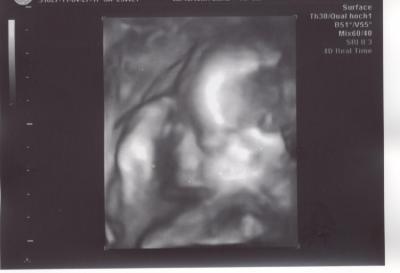

Hallo Mädels. Hatte ja heute 3D US... war gar nicht so einfach, da unser kleiner Mann mit dem Rücken zu meiner Bauchdecke liegt... Die Ärztin hat 45 Minuten geschallt... ein paar süße Bilder sind entstanden... Gruß Cindy.

Bild zu 3D US - Forum für August - Mamis